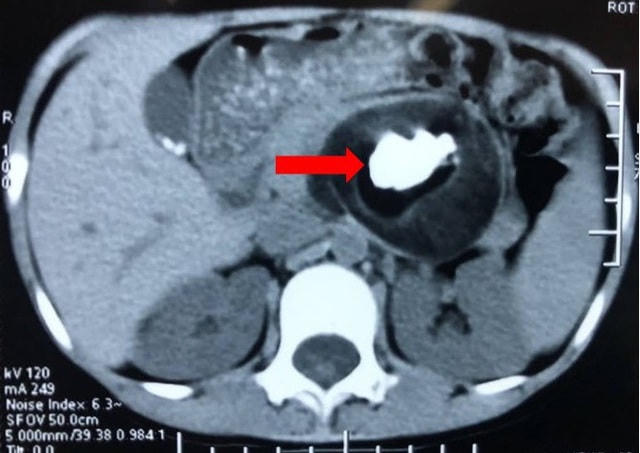

Khối u quái có đường kính 8 cm chứa tóc, răng, xương hàm nằm trong cơ thể bé gái 7 tuổi đã được các bác sĩ phẫu thuật thành công bằng phương pháp nội soi.

Qua thăm khám và kết quả các xét nghiệm cần thiết, các bác sĩ Bệnh viện chẩn đoán trẻ có khối u quái sau phúc mạc và có chỉ định phẫu thuật cắt bỏ khối u.

Sau hơn một giờ phẫu thuật bằng phương pháp nội soi, các bác sĩ đã tiếp cận và cắt bỏ toàn bộ khối u quái đường kính 8cm với các cấu trúc mô cơ thể như răng, xương hàm, tóc, da đầu... Khối u được chuyển làm giải phẫu bệnh cho kết quả u quái thành thục, không có tế bào ác tính.